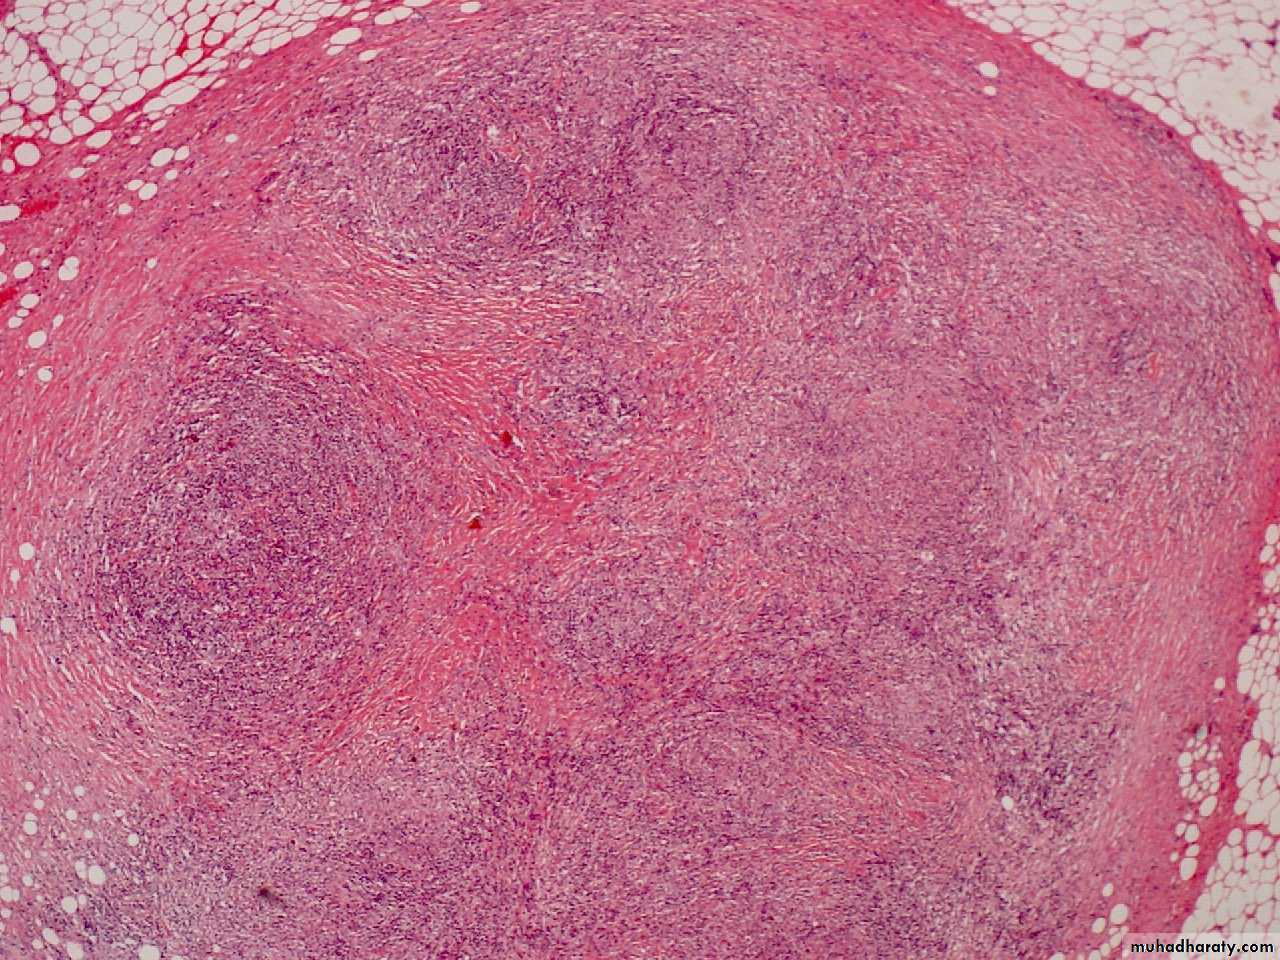

Nodular sclerosing HL

• Most common type Hodgkin's lymphoma in US/Europe

• Usually presents in the anterior mediastinum and neck of young adult females

• Characterized by fibrotic capsule and bands subdividing tissue and

• Lacunar variant Reed Sternberg cell